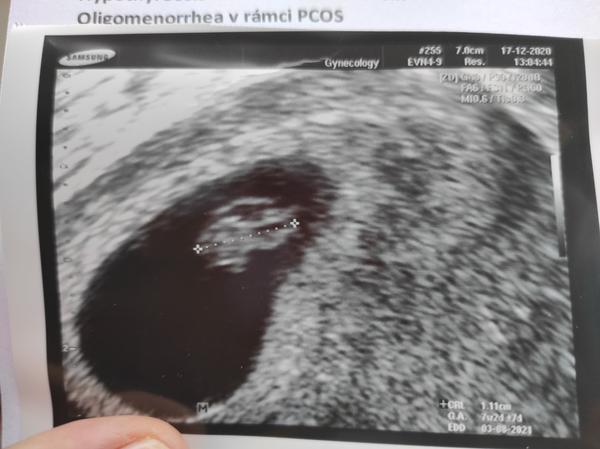

Holčičky. Moc na Vás myslím. Já včera byla na prvním UZ a máme ❤️ jak zvon. Manžel byl se mnou, a celkem si odfouknul že máme jen jedno embryo. 😂😂 Samozřejmě nás trochu vyděsil, manžela víc, že do 3 měsíce se může cokoliv stát. Tak jsem se manžela snažila uklidnit, že rizika nám prostě říct musí. Posílám Vám první fotku, a těším se na Vaše fotky. ❤️❤️ A držím palce.